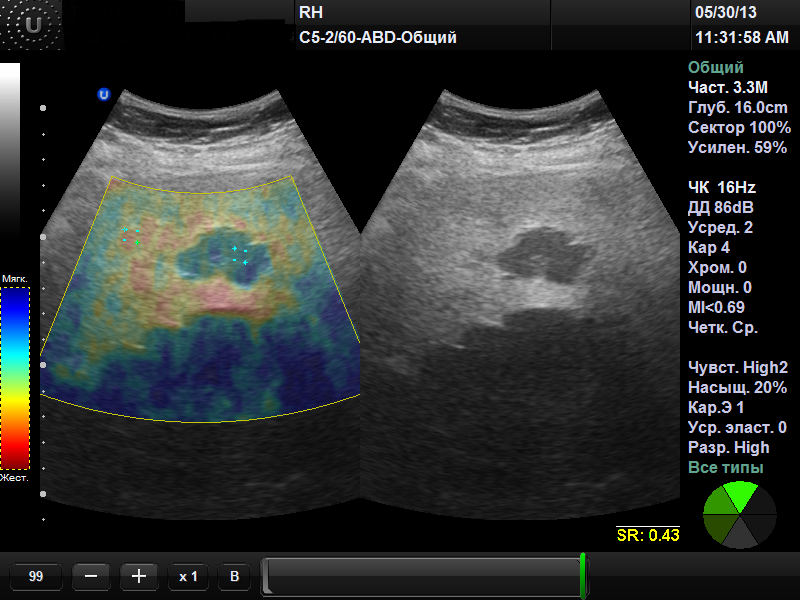

ЭЛАСТОГРАФИЯ (ЭЛАСТОМЕТРИЯ) ПЕЧЕНИ

УЛЬТРАЗВУКОВАЯ ЭЛАСТОГРАФИЯ (соноэластография)

Основной задачей эластографии является дифференциальная диагностика между доброкачественными и злокачественными образованиями.

Один из уникальных современных методов диагностики заболеваний печени – эластография сдвиговой волной доступен в нашем медицинском центре.